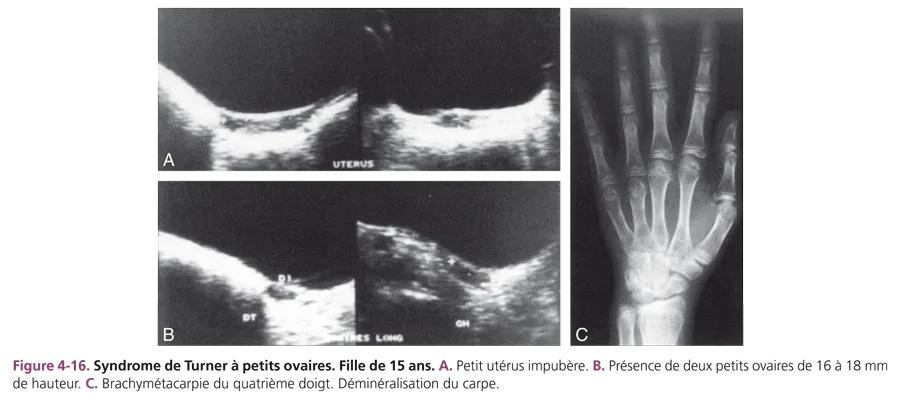

Les hypogonadismes d’origine centrale peuvent se traduire par un impubérisme plus ou moins complet. L’échographie retrouve des organes génitaux internes impubères. L’imagerie recherche une cause centrale et notamment une tumeur de la région sellaire : craniopharyngiome, gliome associé ou non à une neurofibromatose de type I, voire adénome à prolactine. Le syndrome de Kallmann ou dysplasie olfactogénitale est une malformation associant un retard pubertaire et une anosmie ou hyposmie. En IRM, l’antéhypophyse peut être de petite taille et l’hypoplasie (ou aplasie) des bulbes et des sillons olfactifs est objectivée par des coupes fines centrées. L’insuffisance gonadotrope peut s’intégrer dans un panhypopituitarisme congénital. Les hypogonadismes d’origine ovarienne peuvent correspondre à une dysgénésie gonadique dans le cadre d’un syndrome de Turner. Le retard statural y est constant et s’associe à des signes typiques de dysmorphie : cou court avec ptérygium coli, écartement mamelonnaire, cubitus valgus. Les signes osseux classiques sont la brachymétacarpie des IVe et Ve rayons (fig. 4-16C), une trame osseuse grossière et une hypertrophie du condyle interne du genou (signe de Kosowicz). L’examen échographique montre un utérus impubère et des ovaires non individualisables, car ils sont constitués de bandelettes fibreuses, sans follicule. Rarement, les ovaires sont visibles, de petite taille (fig. 4-16A et B). Une échographie rénale doit être couplée à l’étude pelvienne à la recherche de malformations rénales souvent associées (rein en fer à cheval, bifidité, hypotonie pyélo-urétérale, hypoplasie rénale unilatérale). Soixante pour cent des syndromes de Turner présentent une monosomie 45X0 et il existe des mosaïques.